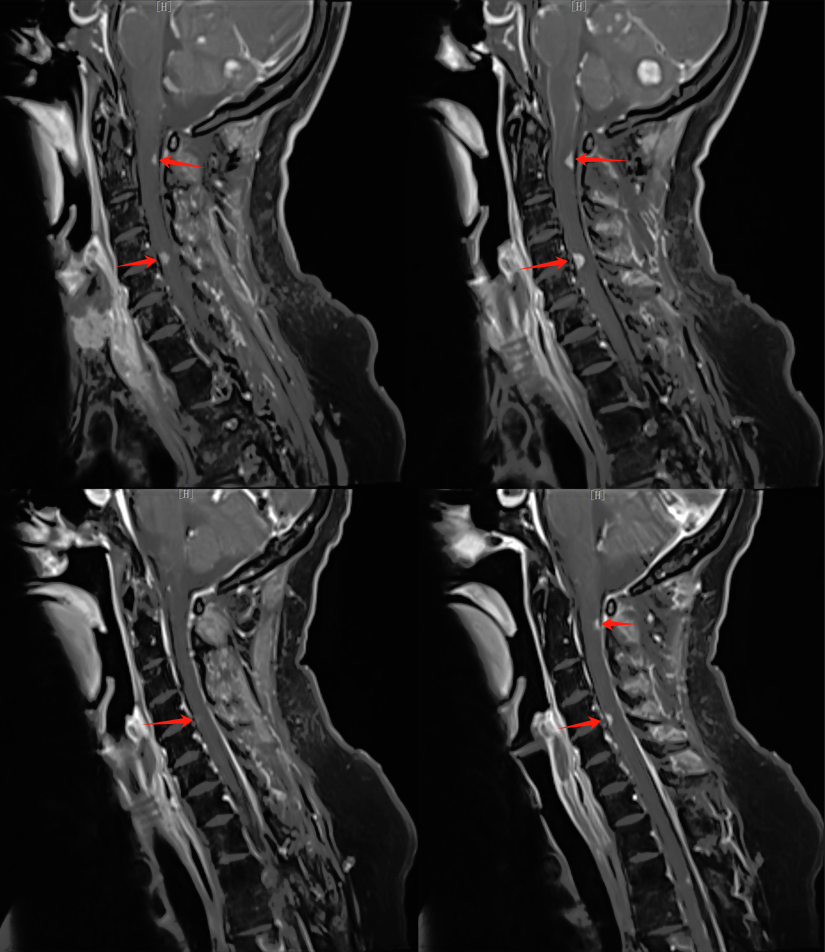

【學科風采】乳腺癌患者千里求醫(yī),成功治療多發(fā)腦轉移瘤、脊髓轉移、腦膜轉移、椎管內多發(fā)轉移結節(jié)、肺炎及肺門轉移患者